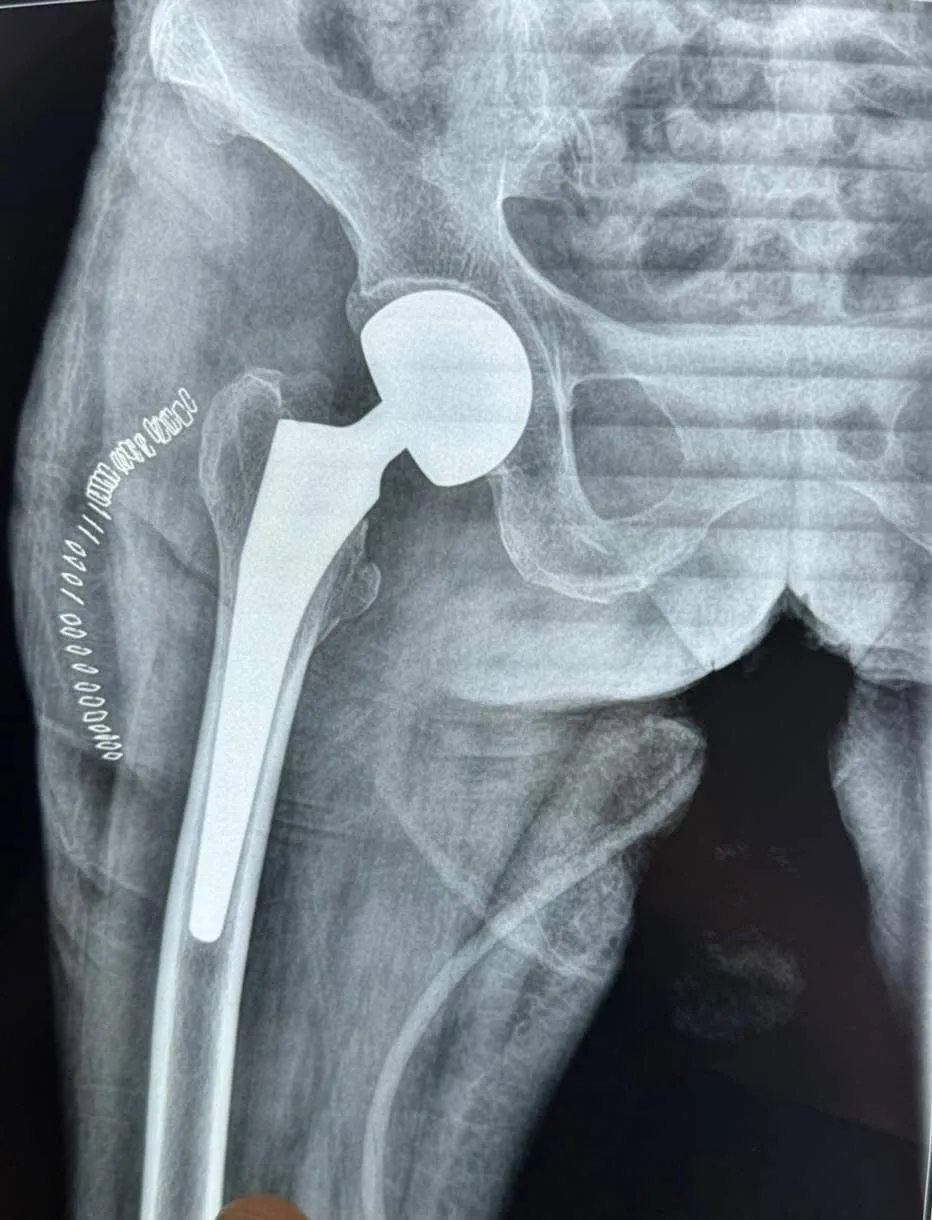

وبحسب بيان للوزارة ورد لوكالة شفق نيوز، فإن المريضة كانت تعاني من كسر في عنق الفخذ، وهو من الإصابات الشائعة والخطرة في هذا العمر المتقدم.

بدورها أكدت إدارة المدينة الطبية أن الفحوصات المختبرية والشعاعية أظهرت وجود ضعف شديد في عضلة القلب لدى المريضة، ما جعل العملية معقدة للغاية، خصوصاً فيما يتعلق بالتخدير والتعامل مع الحالة الصحية الدقيقة.

وأضافت الإدارة أن الفريق الطبي تمكن بفضل خبرته ومهارته من إنجاز العملية بنجاح، وتماثلت المريضة للشفاء بعد خروجها من غرفة العمليات وهي بحالة صحية مستقرة، وذلك بجهود الفريق الطبي والتمريضي وكادر التخدير والكوادر الصحية المساندة في المدينة الطبية.